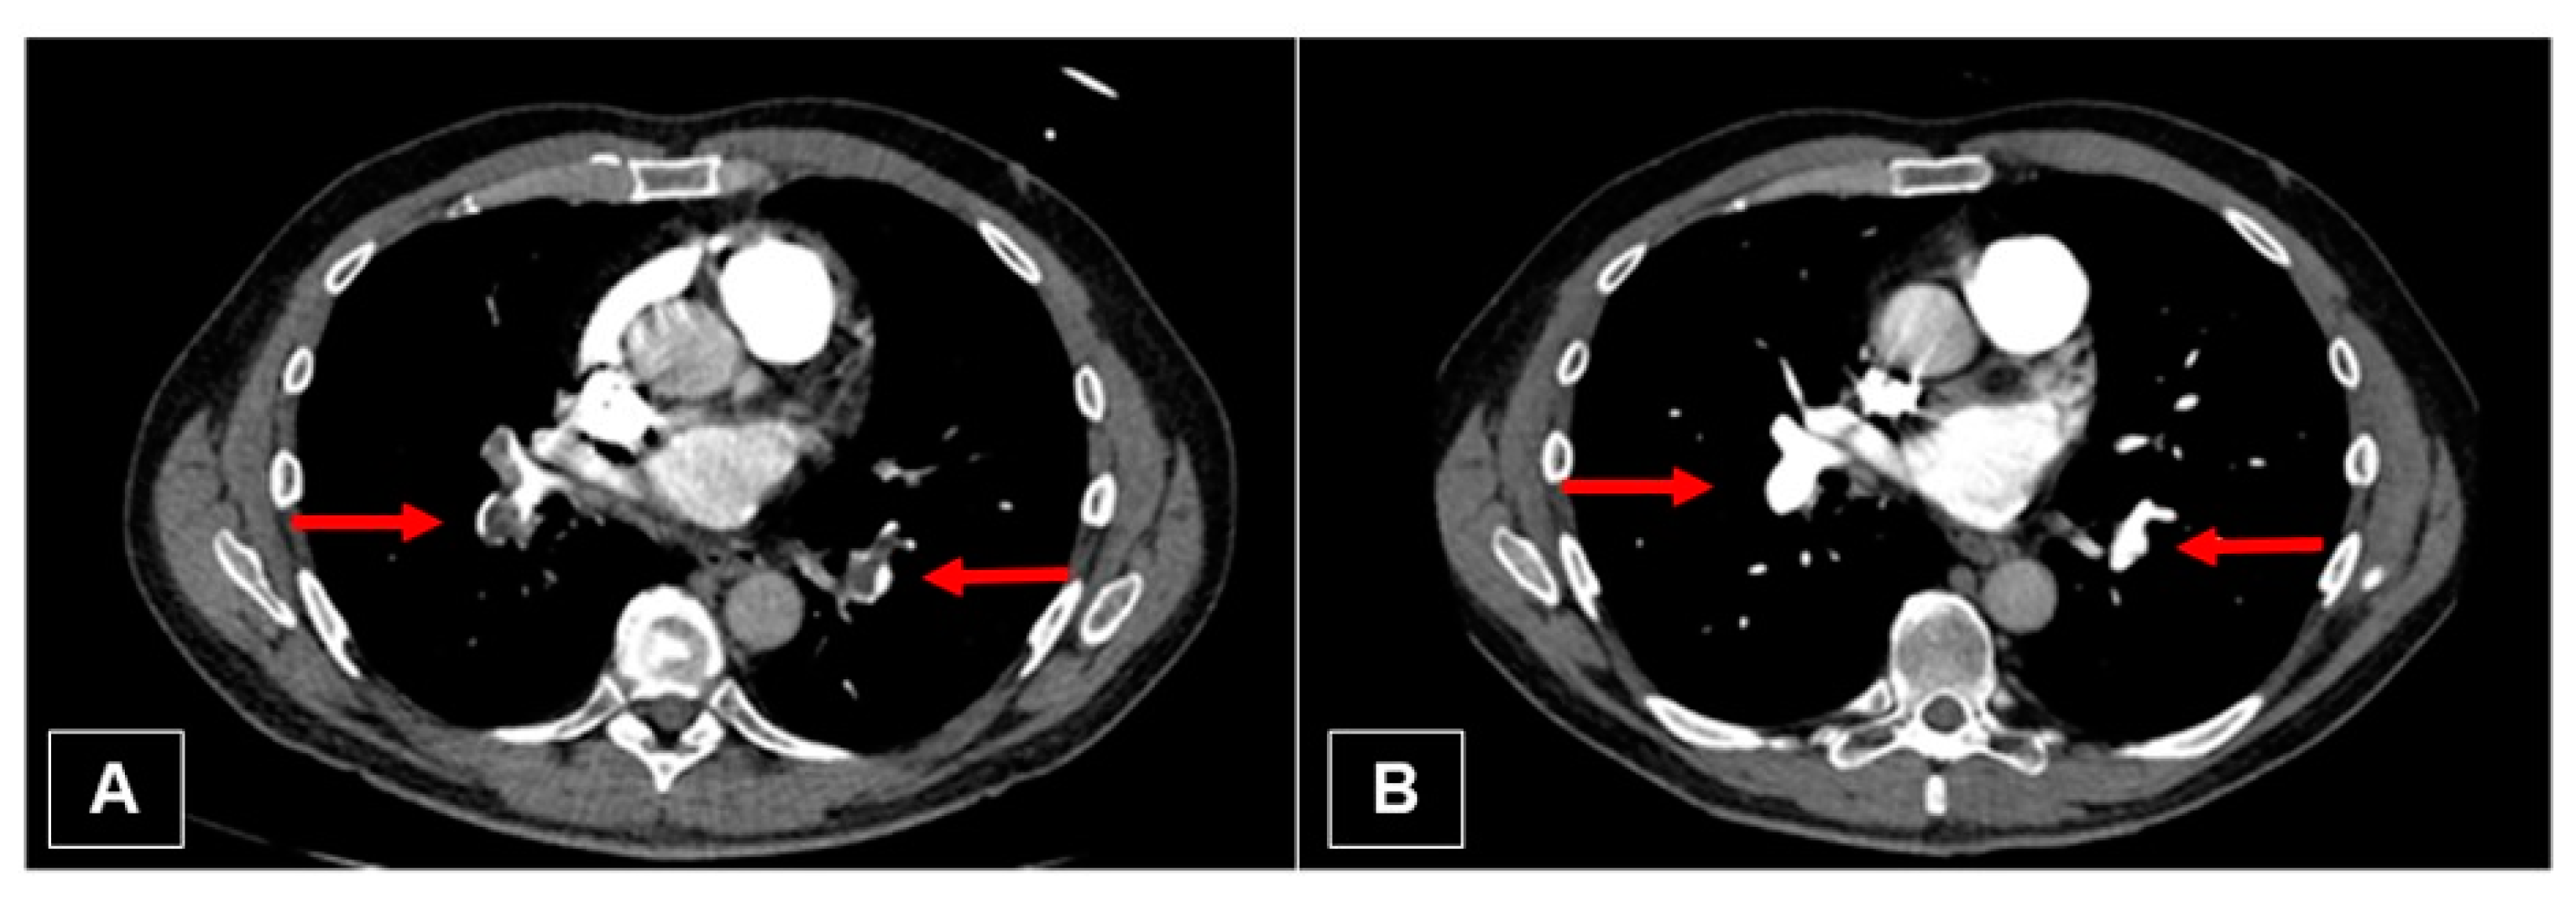

3.3. Imaging

3.4. Computed Tomography Pulmonary Angiography (CTPA)